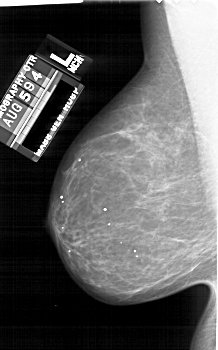

A_1689_1.RIGHT_CC

RIGHT_CC LINES 5836 PIXELS_PER_LINE 3331 BITS_PER_PIXEL 12 RESOLUTION 43.5 OVERLAY

FILE: A_1689_1.RIGHT_CC.OVERLAY

TOTAL_ABNORMALITIES 1

ABNORMALITY 1

LESION_TYPE MASS SHAPE OVAL MARGINS CIRCUMSCRIBED

ASSESSMENT 4

SUBTLETY 3

PATHOLOGY BENIGN

TOTAL_OUTLINES 1

BOUNDARY